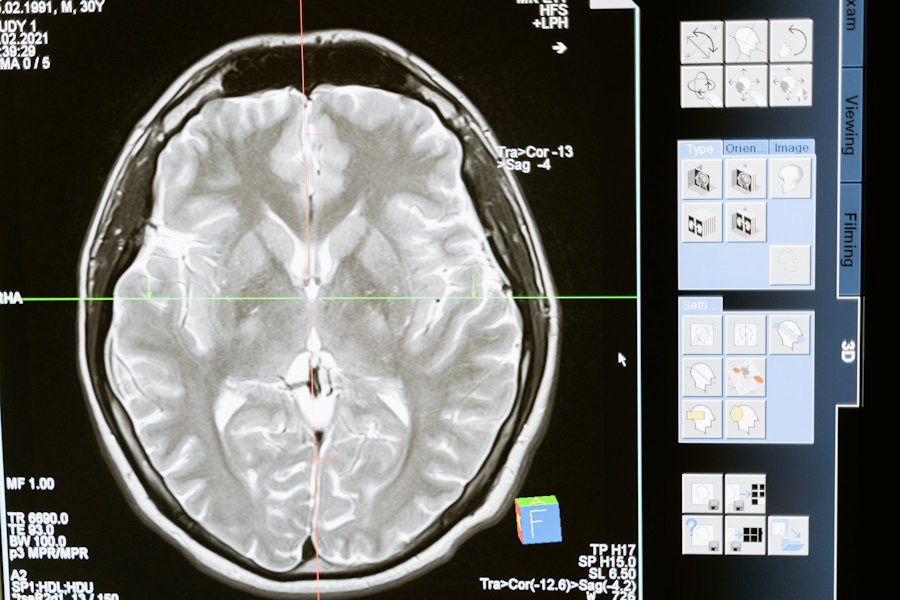

Научные открытия, сделанные исследователями Pitié-Salpêtrière Hospital (Париж, Франция) в области медицины, проливают свет на загадочное явление, известное как "волны смерти" в мозге. Это явление, возникающее при отсутствии кислорода в мозге, вызывает неожиданный всплеск активности, однако оно, вопреки своему названию, не является необратимым признаком смерти.

Согласно порталу Neurobiology of Disease, исследование, проведенное с использованием множества методов, включая многосайтовые внеклеточные локальные потенциалы поля и внутриклеточные записи от идентифицированных нейронов, обнаружило интересные аспекты этого феномена. Под руководством ученых была изучена активность коры мозга крыс при временной аноксии, или отсутствии кислорода.